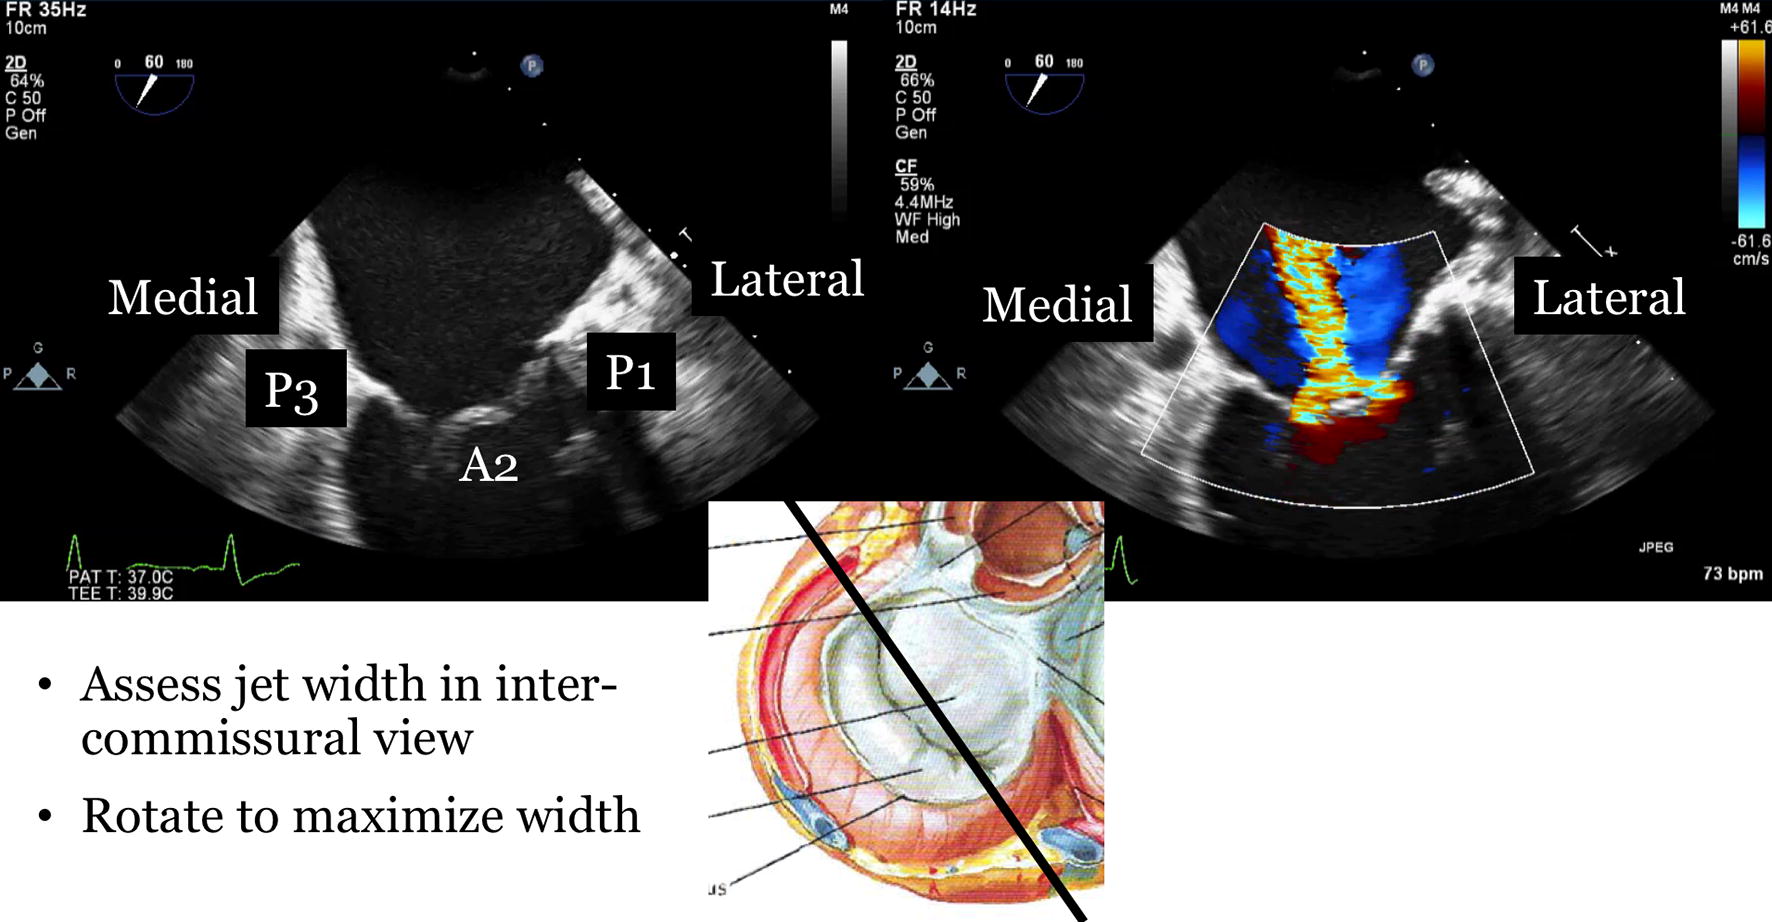

Describe the detailed anatomy of the mitral valve mv using two dimensional 2d transesophageal echocardiography tee based on the american society of echocardiographysociety of cardiovascular anesthesiology guidelines. Assessment of mitral valve dr. Accurate identification the anatomic lesions of the mitral valve echocardiography is pivotal in defining the functional anatomy of the mitral valve surgeon and echocardiographer speaking a common language mutual respect and honesty knowing when to send the.

Perturbations of the normal anatomic relations can result in mitral valve dysfunction table 3. The mitral valve consists of the mitral annulus anterior and posterior leaflets chordae tendineae and the papillary muscles. Assessment of mitral valve anatomy by real time 3 dimensional 3d transesophageal echocardiography tee has proven to be superior compared to 2 dimensional tee 121.

The comprehensive tee examination of the mitral valve consists of a series of eight cross sectional views. Figure 20 1 mitral valve anatomy looking toward the left ventricle from posterior to anterior. Via chordae tendineae small tendons which ensure that the leaflets do not prolapse the valve leaflets are attached to two major papillary muscles anterolateral en posteromedial in the left ventricle.